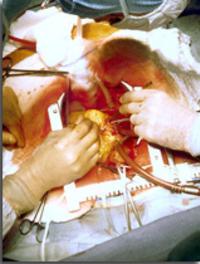

Depuis la publication princeps de Charles Dubost en 1951, on peut traiter chirurgicalement les anévrysmes de l’aorte abdominale (AAA). [...]

Depuis maintenant plus d’une décennie, des techniques de réparation endovasculaire (REV) de l’aorte ont été mises au point pour le [...]

En 2002, l’équipe d’Alain Cribier de Rouen, publiait dans Circulation l’observation du premier patient chez qui avait été pratiqué [...]